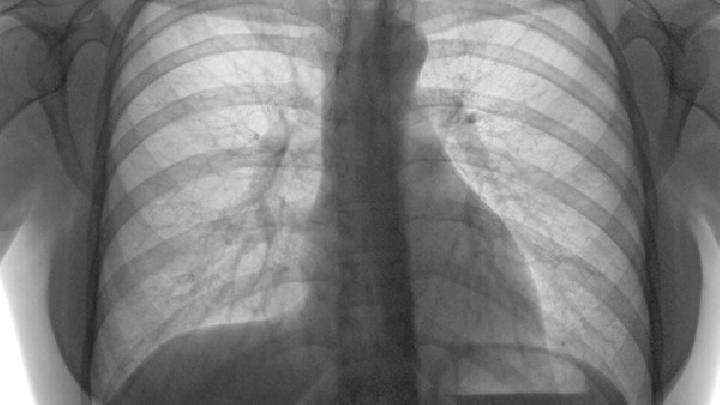

小细胞肺癌又称小细胞未分化癌,是肺癌中恶性程度最高的一种,约占原发性肺癌的1/5。患有该病的患者一般比较年轻,多在40-50岁左右,并且多有吸烟史,男性患者的比率高于女性患者。癌细胞常侵犯管外肺实质,易与肺门、纵隔淋巴结融合成团块。癌细胞生长快,侵袭力强,远处转移早,常转移至脑、肝、骨、肾上腺等脏器。这种类型的肺癌对放疗和化疗比较敏感。

3、胸闷、气短:肿瘤引起支气管狭窄,或肿瘤转移至肺门或纵隔淋巴结,肿大的淋巴结压迫主支气管或气管隆突。